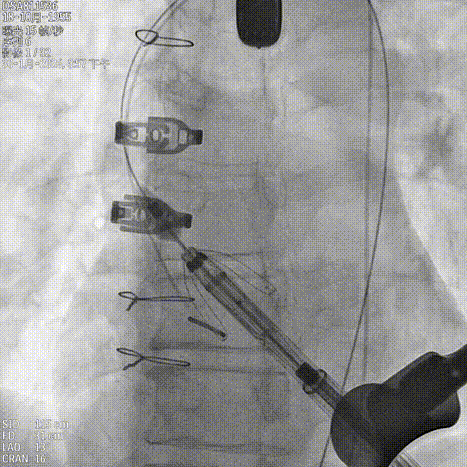

考虑瓣环瓣上结构钙化及锚定能力,选择JS/TAVI-27瓣膜进行植入。手术过程中,团队严格按照标准操作流程实施。自介入器械导入至瓣膜释放完成,器械用时约10分钟。整个过程中,手术团队通过右冠窦居中造影、定位件入窦确认、释放后联合超声与造影评估,确保了瓣膜定位精准、释放平稳,后进行25球囊后扩,瓣膜展开良好。术中超声评估显示无瓣周漏,血流动力学表现良好,手术过程顺利,未出现循环不稳及心律失常等意外情况。

造影确认右窦居中位置

释放定位件入窦

造影确认定位件入窦

调整轴向再次造影确认定位件入窦